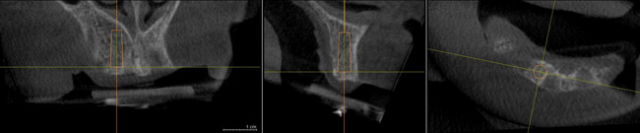

Il Dental Scan è un software che elabora le immagini eseguite per la ricostruzione in tre dimensioni le sezioni delle arcate dentarie. Il termine Dental Scan è comunemente usato per indicare la (TAC nome improprio) per Odondoiatria per diagnostica (arcate dentarie).

Il Dental Scan delle arcate dentarie è utilizzata nel dentale per Chirurgia e Implantologia, e grazie a questo esame è possibile pianificare nei dettagli un intervento Chirurgico, implantare e per diagnostica.

Questo esame permette di avere la visione tridimensionale delle arcate dentali o una parte di esse.